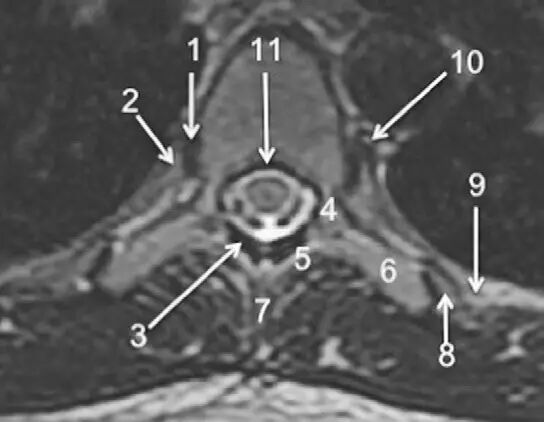

图1正常脊椎的MRI检查,左图为正中矢状位T2WI,右图为T1WI图 2 胸椎 T2WI 轴位图:1,肋椎关节;2,类骨头;3,黄韧带;4,椎弓根;5,椎弓板;6,横突;7,棘突;8,肋横突关节;9,肋结节;10,半奇静脉;11,后纵韧带图 3 腰椎矢状位 T1WI 序列成像:1,脊髓;2,脊髓圆锥;3,马尾;4,蛛网膜下腔;5,硬膜外脂肪;6,黄韧带;7,棘间韧带;8,棘上韧带;9,椎体静脉丛;10,硬膜外静脉丛;11,硬膜外脂肪;12 主动脉图 4 L5/S1 水平轴位 T1WI 序列成像:1,腰肌;2,L5 神经根(前支);3,L5 神经根(后支);4,黄韧带;5,蛛网膜下腔;6,马尾神经根;7,小关节面;8,髂腰韧带;9,左髂外静脉;10,左髂外动脉;11,右髂外动脉;12,右髂外静脉;13,多裂肌;14,竖脊肌组图 5 腰椎旁矢状位 T1WI 序列成像:1,腰静脉;2,腰动脉;3,椎间孔静脉;4,脊神经节后根;5,椎间孔静脉;6,关节面;7,多裂肌;8,竖脊肌群;9,胸腰筋膜,后层图 6 胸椎 T1WI 序列成像:1,胸髓;2,蛛网膜下腔;3,硬膜外脂肪;4,黄韧带;5,多裂肌;6,棘突;7,硬膜外静脉;8,棘上韧带图 7 胸椎矢状位 T2WI 序列成像:1,胸髓;2,蛛网膜下腔;3,黄韧带;4,多裂肌;5,棘突;6,棘上韧带;7,椎体静脉;8,脊髓圆锥;9,马尾图 8 胸椎旁矢状位 T2WI 序列成像:1,硬膜囊后壁;2,硬膜外脂肪;3,黄韧带图 9 胸椎轴位 T2WI 序列成像:1,主动脉;2,半奇静脉;3,奇静脉;4,椎间孔静脉;5,胸肋间血管;6,脊神经节后根;7,椎体静脉;8,后纵韧带;9,脑脊液流动伪影;10,多裂肌;11,背最长肌;12,斜方肌图10 胸椎旁矢状位 T2WI 序列成像:1,椎间孔静脉;2,胸椎旁肋间动静脉;3,神经根;4,上关节突;5,下关节突;6,关节面;7,椎弓峡部;8,椎弓根;9,黄韧带;10,竖脊肌群;11,斜方肌——本期完——